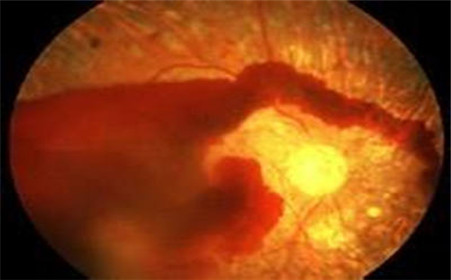

玻璃体出血是眼外伤或视网膜血管性疾病造成视力危害的一种常见并发症,是一种严重影响视力的眼睛血管疾病,临床症状主要以视野缺损,或视线模糊等视力障碍表现。

通常当玻璃体出血后,通常经过一段时间玻璃体内的血液会吸收而弥散,玻璃体颜色也会变淡,会逐渐变得透明,较多血液的吸收则需要6个月或1年以上,在没有明显眼底病变时,视力可能完全或大部分恢复,但如果是大量玻璃体出血时,就要小心可能有失明的疑虑。